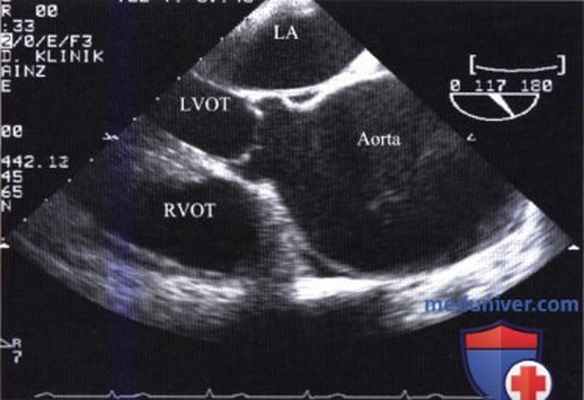

Видео. Острое расслоение восходящей аорты (тип A) у 66-летнего больного. Чреспищеводная ЭхоКГ вдоль длинной (a) и короткой (b) оси сердца. Расслаивающая мембрана достигает плоскости аортального клапана.

Методика чреспищеводной эхокардиографии. Чреспищеводная ЭхоКГ при подозрении на расслоение грудной аорты начинают с визуализации восходящей аорты при повороте датчика под углом 120°, а затем поворачивая плоскость лоцирования под углом 45-50 и 0°. В просвете аорты виден отслоившийся внутренний слой (разделительная мембрана, отделяющая истинный и ложный просвет), который отличается значительной подвижностью.

При выявлении разделительной мембраны необходимо исследовать аортальный клапан и измерить аортальное кольцо. После этого с помощью цветового допплеровского картирования пытаются выявить недостаточность аортального клапана, которая имеется у 70% больных с расслоением восходящей аорты, определить ее степень и уточнить причину. На рисунке ниже показаны три механизма развития аортальной недостаточности при расслоении аорты типа А, не считая двустворчатого аортального клапана; знание этих механизмов имеет значение при выборе способа реконструкции аорты. Кроме того, следует визуализировать проксимальный отдел коронарных артерий и уточнить, где они начинаются - в ложном просвете или в истинном. Затем, поворачивая зонд с датчиком, сканируют нисходящую аорту в различных плоскостях на всем протяжении от поддиафрагмального отдела до дуги.